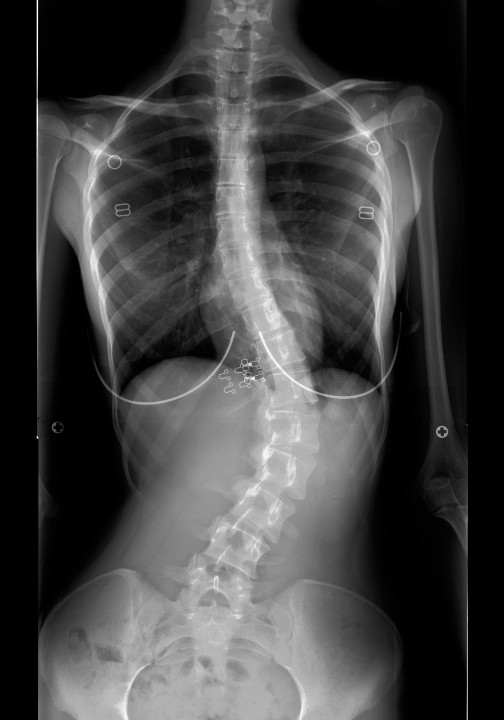

Pre-op Post-op